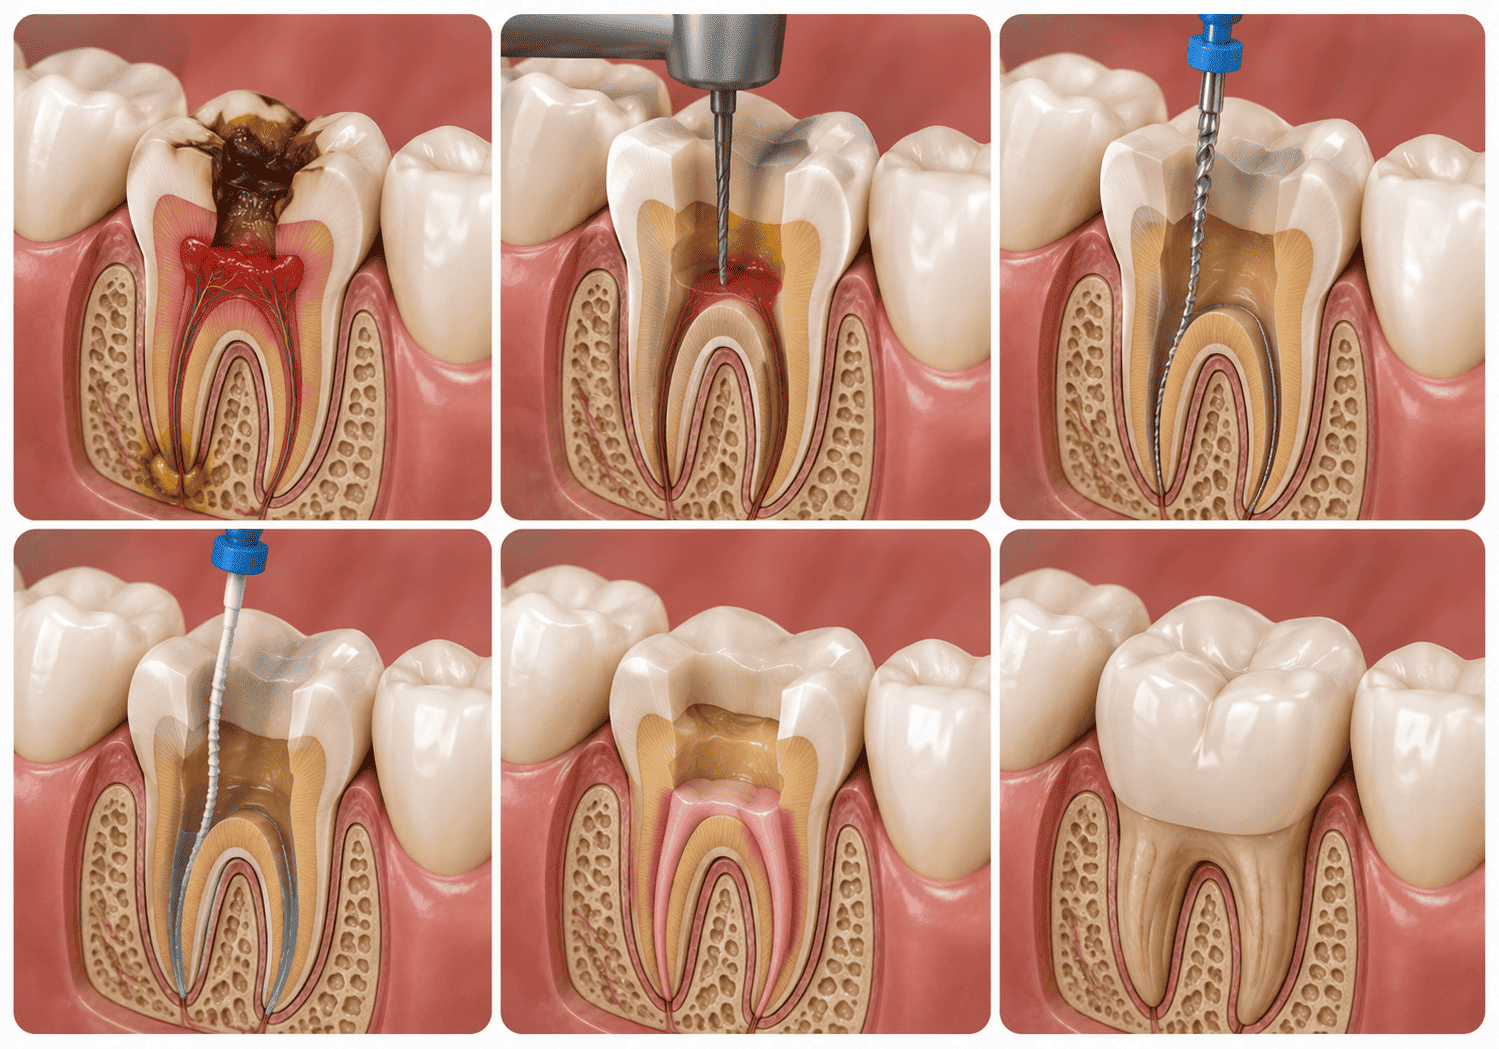

রুট ক্যানাল চিকিৎসা (Root Canal Treatment / RCT)